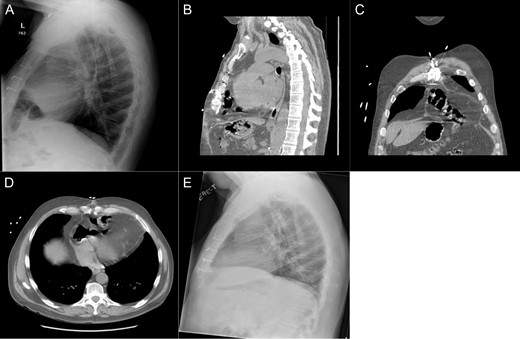

Patient #1 is a 60-year-old male with a history of gastroesophageal reflux disease and ischemic cardiomyopathy. He underwent placement of a Heartmate II LVAD in 2013 before undergoing an orthotopic heart transplant (OHT) 2 months later. After an initially uncomplicated course, he presented to the emergency department 1 year following transplant with reflux, epigastric pain and a recent 10-pound weight loss. Prior endoscopic evaluations had been normal; however, a chest X-ray was suggestive of intrathoracic bowel. A subsequent CT scan demonstrated an intrapericardial hernia containing the transverse colon (Fig. 1A–D) and the patient was taken to the operating room for a robotic diaphragmatic hernia repair.

Imaging from Case #1. (A) Preoperative X-ray demonstrating loop of bowel in the thoracic cavity. (B) Preoperative CT scan, saggital view of diaphragmatic defect. (C) Preoperative CT scan, coronal view demonstrating colon passing through diaphragmatic defect. (D) Preoperative CT scan, axial view demonstrating intrapericardial transverse colon. (E) Postoperative X-ray demonstrating reduction of hernia contents.

The patient’s postoperative course was uneventful. Postoperative imaging showed apparent resolution of the diaphragmatic defect (Fig. 1E). At 1 month, the patient was noted to be tolerating a regular diet without complaints of any dysphagia or reflux.